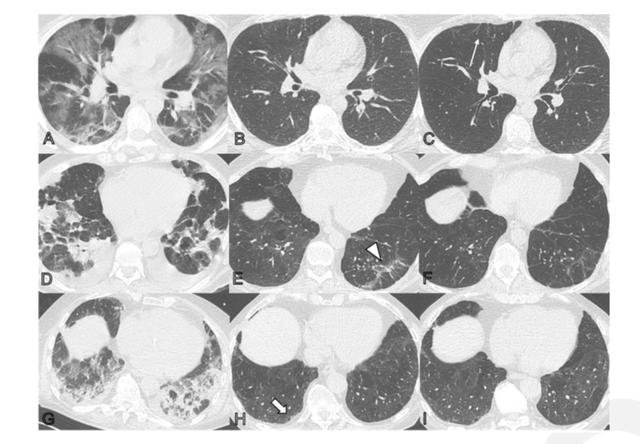

A-C为一名44岁男性患者CT;D-F为一名68岁男性患者CT;G-I为一名79岁男性患者CT。从左至右分别为发病时、随访2个月和随访1年。

论文指出,急性COVID-19肺炎的放射学表现主要为毛玻璃样混浊(GGO)和局灶性实变。COVID-19肺炎早期组织学改变为斑片状急性肺损伤伴肺泡II型细胞增生和肺泡间毛细血管增大。此前有研究发现,COVID-19肺炎后4-10周的CT随访显示,45-63%的患者肺实质异常。然而,长期肺转归尚不清楚。

这49名参与者中,有31人(34%)显示细微的胸膜下网状、毛玻璃混浊或两者兼有;另外18名参与者(20%)患者显示广泛的毛玻璃混浊物、网状、支气管扩张或微囊性改变。